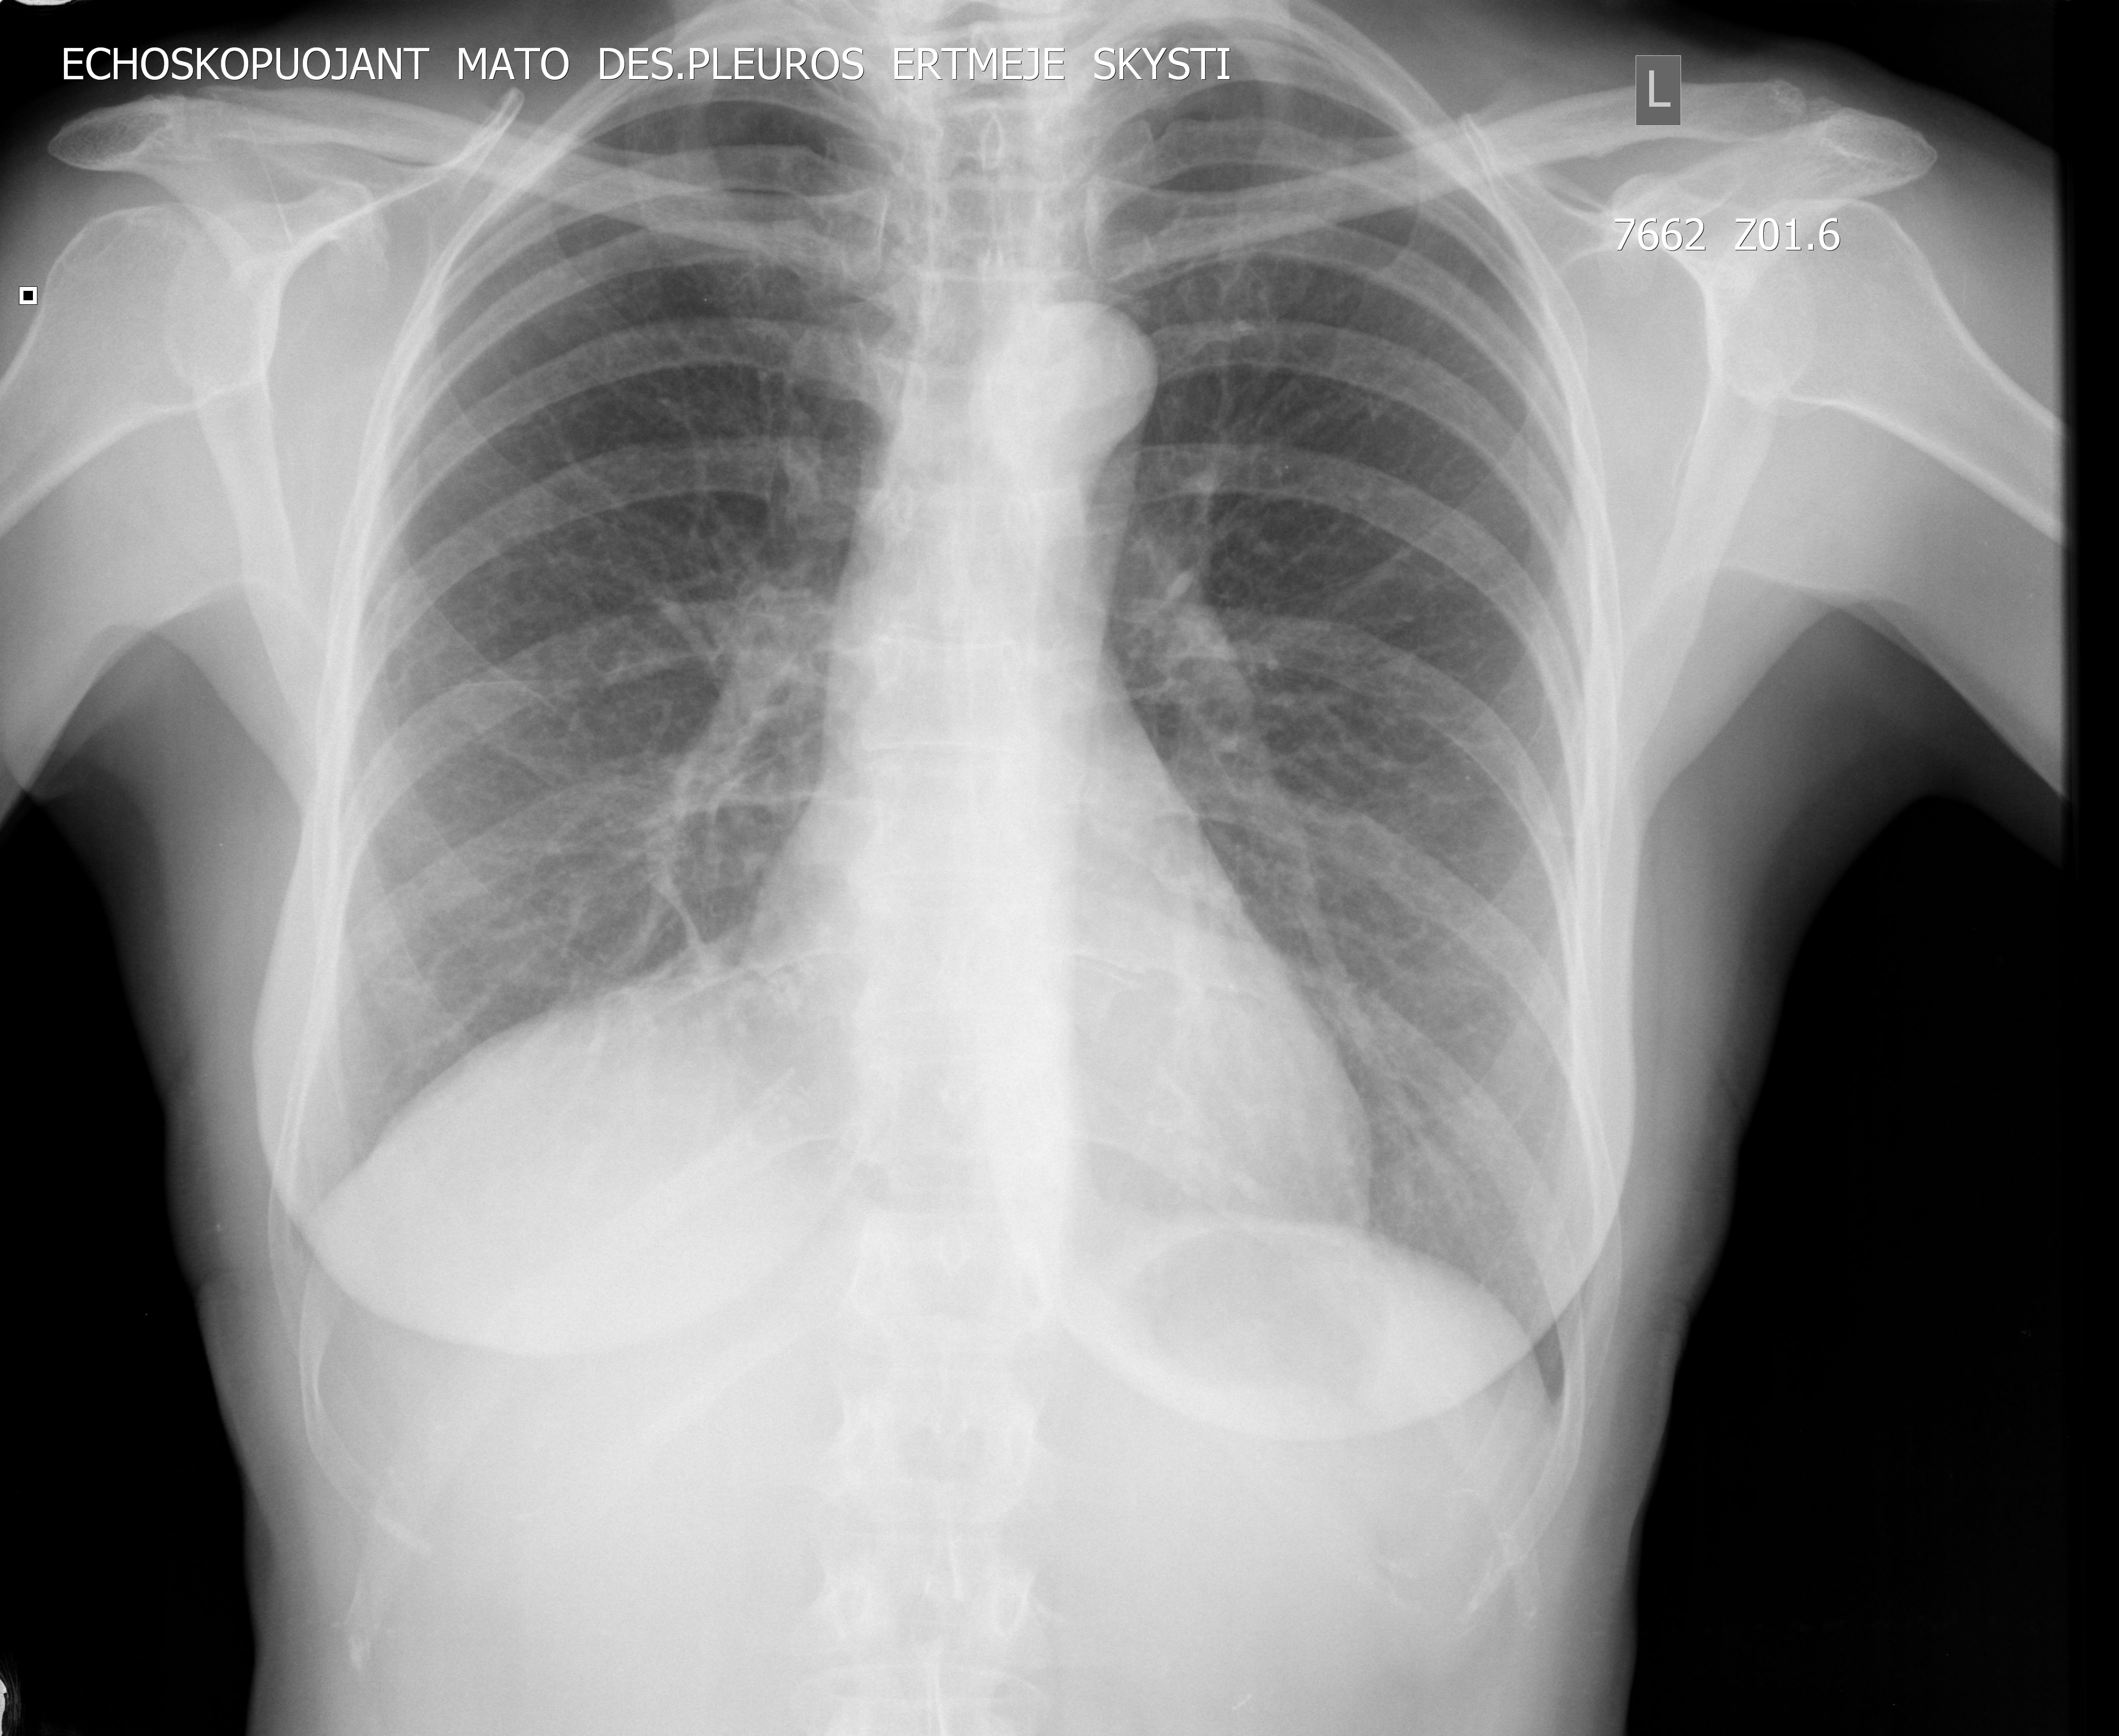

Женщина средних лет. Профилактическое УЗИ. Жалоб не предъявляет.

Ответ радиолога по РГ

Спайки vs Липома vs Другое в правом кардиодиафрагмальном синусе

ro -grama - Krūtinės ląstos organų 2-jų krypčių rentgenogramos Pleuros sinusai laisvi. Dešinėje kardiodiafragminis sinusas seklus - sąaugos ar lipoma ar kita? Dešinėje deformuota diafragma dėl dalinės relaksacijos? Plaučių piešinys pagausėjęs deformuotas. Šaknys struktūrinės. Širdis - n.y. Ao - suintensyvėjusi.